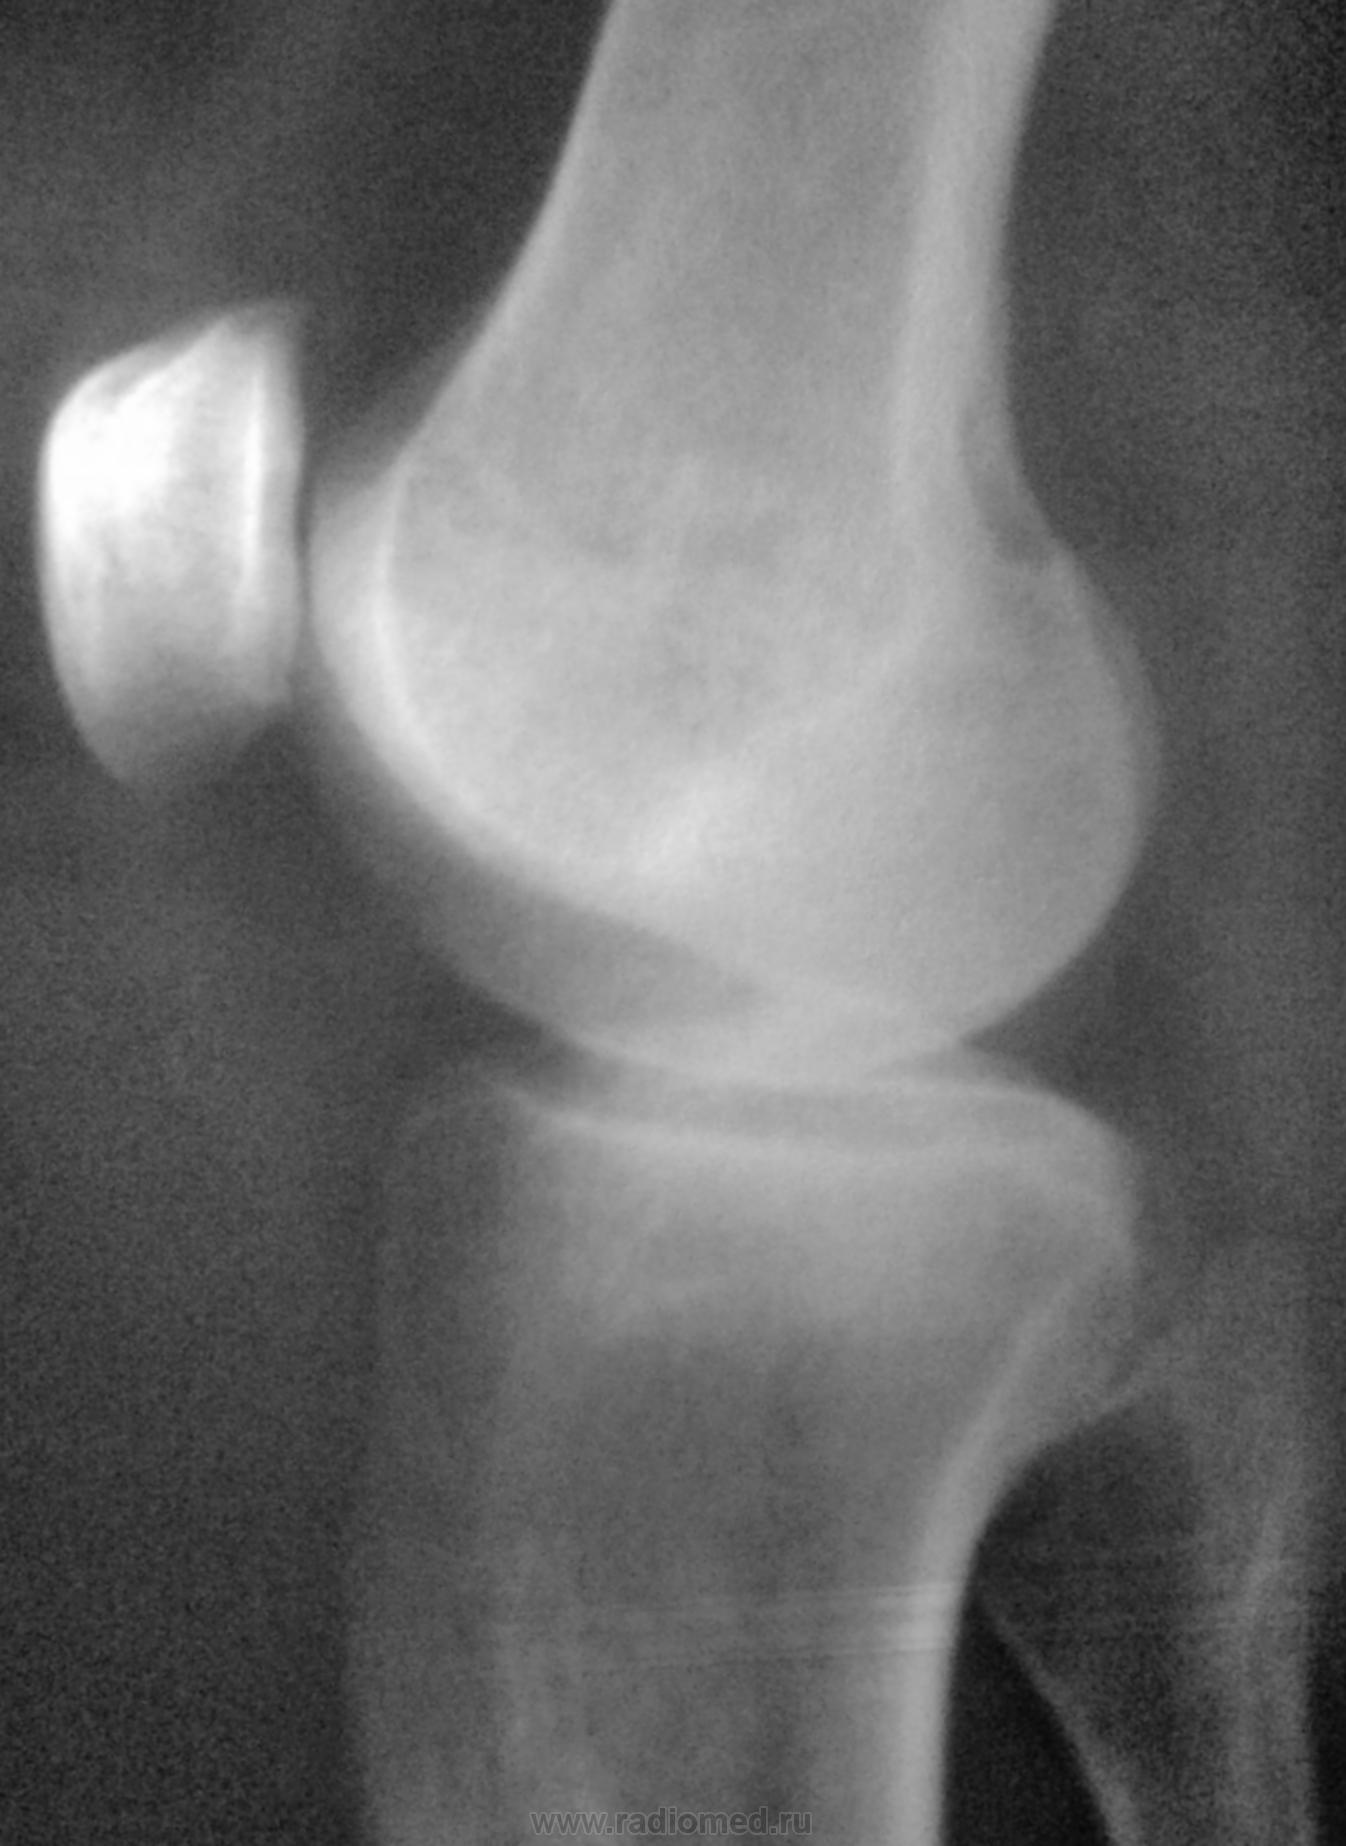

Пол пациента: Женский пол Тип патологии: Другое Область исследования: Скелетно-мышечная система Методы исследования: Rg Доброго времени суток! Коллеги, подскажите, что это может быть возле медиального надмыщелка бедренной кости? Пациентку 65 лет направил хирург с ДОА. Заранее спасибо. https://radiomed.ru/sites/default/files/styles/case_slider_image/public/user/12/12.foto0170-1.jpg?itok=EaLMu7dQ https://radiomed.ru/sites/default/files/styles/case_slider_image/public/user/12/13.foto0174.jpg?itok=p2Fa3XXR ID:24113 Пнд, 29/10/2012 - 23:01 #1 Almo Не на сайте Был на сайте: 9 часов 51 минут назад Зарегистрирован: 28.09.2008 - 18:50 Публикации: 8256 Тень Штида( внутренный мыщелок бедра). Пнд, 29/10/2012 - 23:02 #2 Андрей Юрьевич Не на сайте Был на сайте: 6 дней 14 часов назад Зарегистрирован: 16.11.2008 - 22:16 Публикации: 18098 Пеллегрини - Штиды болезнь http://www.radiomed.ru/publications/kss-pellegrini-shtida-bolezn Хотя в наше время считалось, что не болезнь это, а так, синдром. Андрей Юрьевич Пнд, 29/10/2012 - 23:05 #3 И.Бондаренко Не на сайте Был на сайте: 2 дня 7 часов назад Зарегистрирован: 13.09.2011 - 22:55 Публикации: 9206 +1 Втр, 30/10/2012 - 05:58 #4 Петр Николаевич Не на сайте Был на сайте: 3 года 10 месяцев назад Зарегистрирован: 15.03.2011 - 13:22 Публикации: 150 Болезнь Пеллегрини - Штида +1 Втр, 30/10/2012 - 19:31 #5 maker4ik Не на сайте Был на сайте: 8 лет 7 месяцев назад Зарегистрирован: 19.10.2011 - 17:49 Публикации: 2682 Плюсую к Пеллегрини-Штида.

Тень Штида( внутренный мыщелок бедра).

Пеллегрини - Штиды болезнь http://www.radiomed.ru/publications/kss-pellegrini-shtida-bolezn Хотя в наше время считалось, что не болезнь это, а так, синдром.